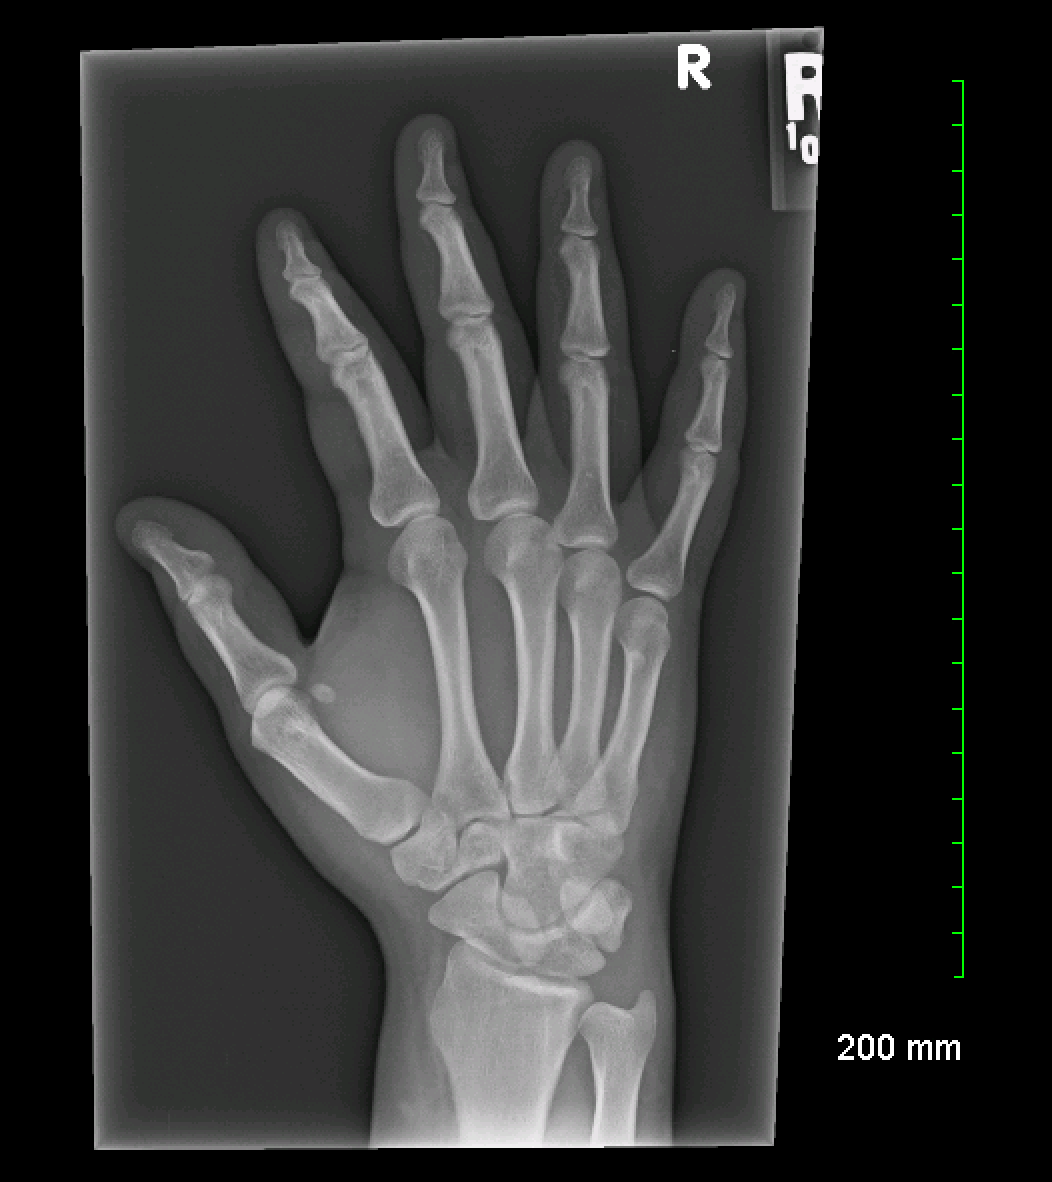

x ray of right hand and wrist

Posts: x ray of right hand and wrist